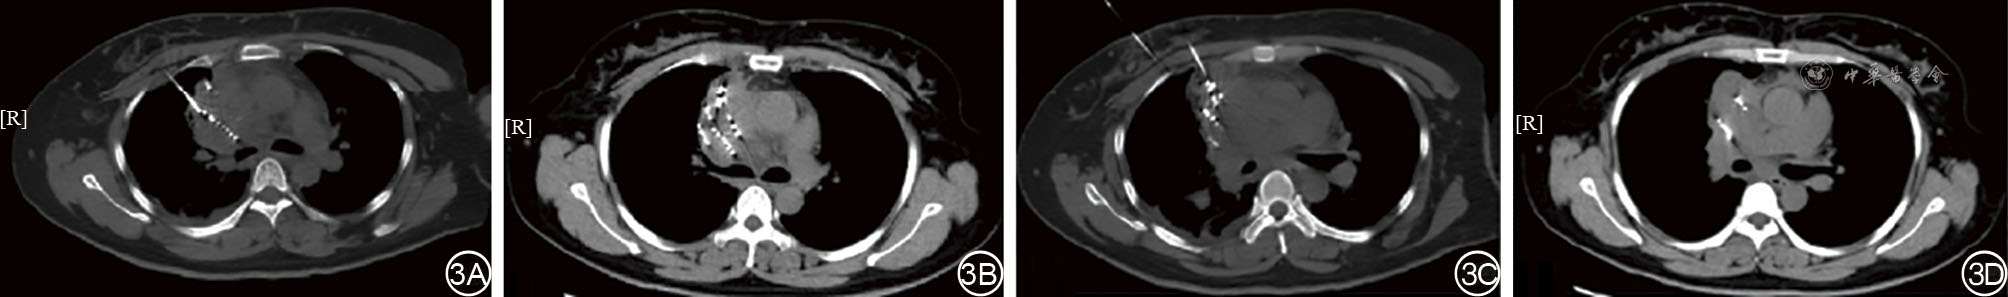

We present a case of a 40-year-old female patient with midline carcinoma, who was admitted for chest pain and cough and diagnosed with concurrent mediastinal and pulmonary metastases. Single-agent chemotherapy proved ineffective and her clinical symptoms aggravated, accompanied by tracheal and superior vena cava compression. Following multidisciplinary consultation, CT-guided 125Ⅰ seed implantation was initially performed. Local tumors regressed postoperatively while partial pulmonary metastatic lesions progressed, prompting seed reimplantation combined with bronchial arterial chemoembolization, followed by concurrent anlotinib targeted therapy and sintilimab immunotherapy. After six months of comprehensive treatment, the thoracic tumors resolved, lymph nodes shrank, radiological evaluation indicated partial response, and the patient's clinical symptoms were significantly relieved. This case demonstrates that the integrated regimen of interventional local therapy plus targeted and immunotherapy offers a viable therapeutic approach for inoperable midline carcinoma patients with refractory conventional chemotherapy, enabling rapid symptom relief and improved treatment efficacy.